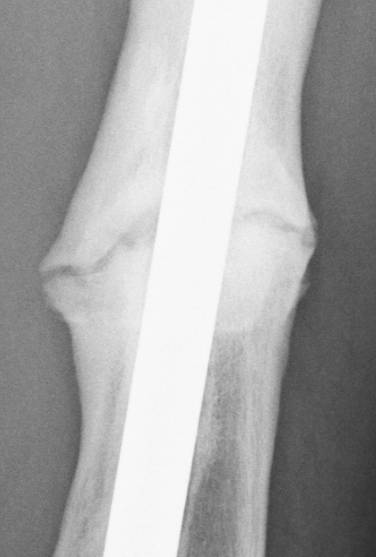

June 22, 2010 X-ray update

Forive me people for I have sinned. It has been two years since my last update. But seriously, there is much improvement to report. Based on activity and how it feels things are progressing very well. The x-rays also show more bone growth which adds to the good sign.

Feb. 21, 2008 June 22, 2010